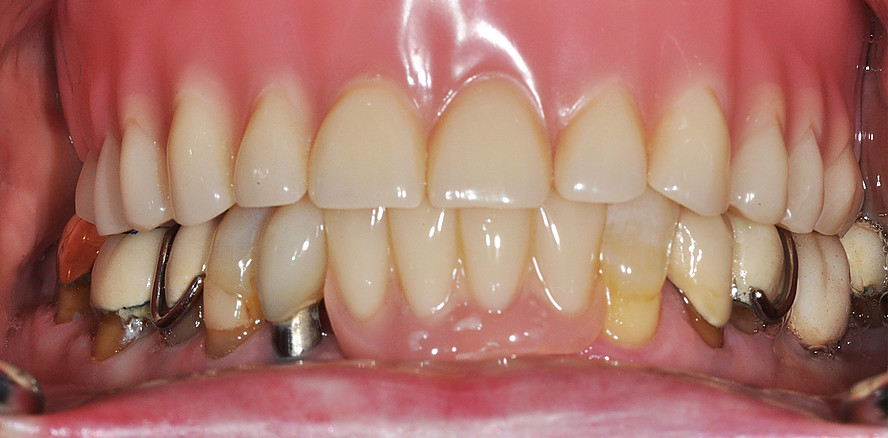

Die implantatprothetische Versorgung zahnloser Kiefer mit abnehmbaren Prothesen gilt als einfach und vorhersagbar, mit deutlicher Verbesserung der Lebensqualität der Patienten. In der Praxis erweisen sich aber präfabrizierte Verankerungselemente wie Kugelkopf und Locator oftmals als problematisch.

Die Insertion von zwei zahnärztlichen Implantaten zur Verankerung einer abnehmbaren Deckprothese stellt eine kosteneffektive Therapie dar, welche die Kaufunktion verbessert und zu hoher Patientenzufriedenheit führt, weshalb diese Versorgung in mehreren Ländern als „standard of care“ angesehen wird.1, 6, 14 Die dabei genutzten Verankerungselemente, welche die Prothese mit den Implantaten abnehmbar verbinden, sind entscheidend für den Prothesenhalt, die Patientenzufriedenheit und den klinischen Erfolg.14 Stege, Kugelkopf­anker und Locatoren werden hierfür häufig genutzt und führen zu einer Verbesserung der mundbezogenen Lebensqualität.4–6, 14 Die in Deutschland weitverbreiteten Doppelkronensysteme konterkarieren aufgrund der hohen Herstellungskosten die Grundidee einer kosteneffektiven Grundversorgung.8, 10, 15

Für die einzelnen Verankerungselemente werden weit gestreute Haftkräfte berichtet, wobei der Haftkraftverlust das dominierende klinische Problem15 darstellt und zu wiederholten Interventionen führt.12, 13 Dies tritt insbesondere bei nicht parallel inserierten Implantaten auf, weshalb die Industrie sogenannte „extended range“ Verankerungselemente anbietet, die Dispa­rallelitäten kompensieren sollen. Gemäß einer retrospektiven Studie mit dreijähriger Beobachtungsdauer gelingt dies jedoch nicht.9 Ein weiterer Faktor dabei scheinen Übertragungsfehler der Patientensituation auf ein Labormodell zur Herstellung des Zahnersatzes zu sein.7

Eine randomisierte klinische Studie zu implantatgestützten Unterkieferdeckprothesen beschrieb den Verschleiß der Verankerungselemente als häufigste Komplikation.1 Ähnliche Ergebnisse werden aus einer randomisierten klinischen Studie an 18 Pa­tienten über neun Jahre Beobachtungsdauer mit 136 prothetischen Komplikationen berichtet.11 Dies wird ebenfalls von einer retrospektiven Studie an Kugelkopfankern bzw. Locatoren gestützt, welche Behandlungsnotwendigkeiten aufgrund von Verschleiß des Verankerungselements als häufigste Komplikation beschreibt.2 Ein hoher Anteil der nötigen Interventionen scheint dabei bereits in der Anfangsphase bis zu einem Jahr aufzutreten, was mit der Findung einer für den Patienten adäquaten Haltekraft assoziiert sein dürfte.3, 15

Pfeilerdisparallelitäten und Transferfehler verhindern derzeit, dass neben den guten Überlebensraten implantatgetragener abnehmbarer Deckprothesen auch hohe Erfolgsraten unter Nutzung vorgefertigter Verankerungselemente erzielt werden. Ebenso stellt die Einstellung vorhersagbarer Retentionswerte ein klinisches Problem dar, da diese bei mehreren und zudem nicht parallelen Implantaten lediglich durch Ausprobieren erarbeitet werden kann. Aufgrund der geringeren Bauhöhe und ihrer Rotationssymmetrie sind Kugelkopfanker vorteilhafter und könnten durch Weiterentwicklung zum Ausgleich von Implantatdivergenzen die genannten Probleme lösen.